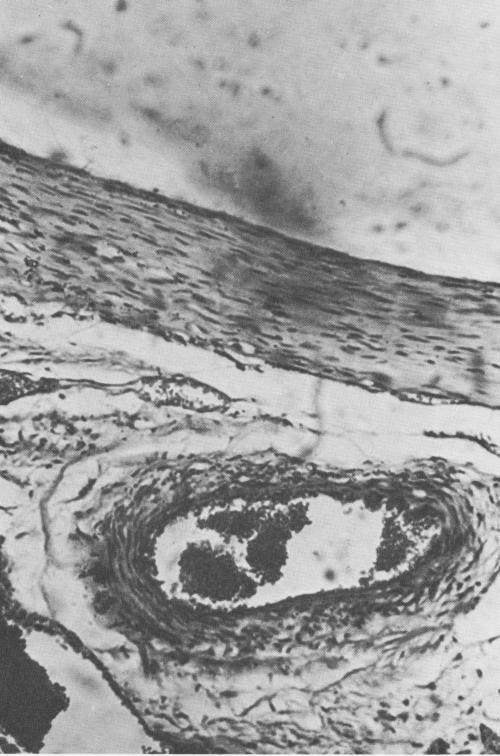

Fig. 4-70. At the base of the implant the connective tissue appears to be highly organized. (Courtesy K. R. Blakey, Howard University.)

2 Highly organized connective tissue near base of endosseous implant